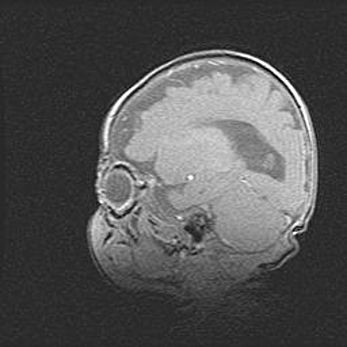

Множественные кисты обоих полушарий головного мозга, наибольшая из них в правой затылочной области. Ассиметричная атрофическая гидроцефалия.

Возраст: 7 месяцев

Вес: 5660 г

Пол: мужской

Окружность головы: 41,5 см

Срок гестации: 28-29 недель

Кисты головного мозга развиваются в результате многоочаговых некрозов вещества мозга и возникают вследствие перенесенной перинатальной инфекции, менингитов, энцефалитов, асфиксии, родовой травмы, расстройств мозгового кровообращения различного генеза. Образованию кист в веществе головного мозга плодов и новорожденных способствуют такие факторы, как высокое содержание в нем воды, недостаточная (или отсутствие) миелинизация и слабая астроглиальная реакция на повреждение.

Кисты могут сочетаться с гидроцефалией и другими поражениями головного мозга.